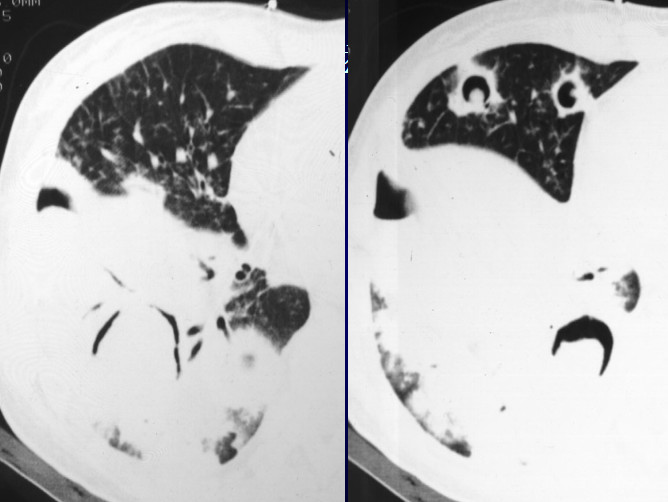

病例1:肺结核

X线胸片表现为在两侧中上肺有斑片状阴影,隐约可以看到小的空洞样病变。CT显示的很清楚,可以看两肺尖空洞,周围有小的点状播散病灶。在上叶前段、左上叶尖后段也有空洞,这些空洞的周围可以看到树芽征,小叶中心的病变。所以这是典型的以中上肺分布的伴支气管播散病灶,为典型的肺结核病变。

8f4450ce4d4da59570a3e19355c2ef50.jpg

cbc2d79e9ae9dbaf2f1eaa48fe964705.jpg